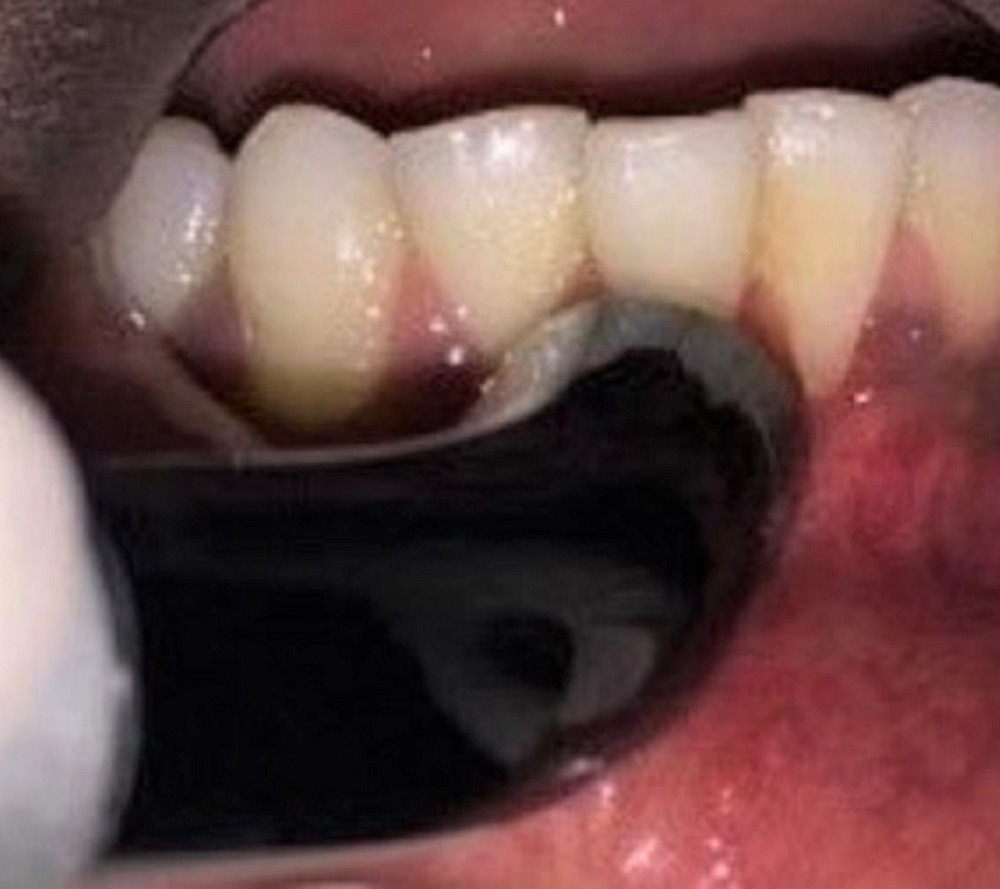

Postoperative protocol

The patients were advised to take an analgesic (aceclofenac 100 mg, 3 times a day for 5 days) and an antibiotic (amoxicillin 500 mg, 3 times a day for 5 days) post-surgery, and instructed to refrain from tooth brushing and flossing until the removal of the sutures. They were also instructed to rinse their mouth with chlorhexidine mouthwash (0.12%) twice daily for a period of 1 month. The sutures were removed 7 days post-surgery (Figure 7 and Figure 8).